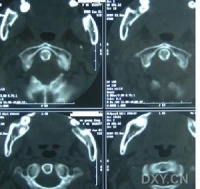

2.继发性神经性斜颈颈椎肿瘤、损伤、骨关节炎、颈椎结核等可导致本病。颈椎间盘突出、枕大神经炎等,因颈部神经及肌肉受刺激,导致强直性斜颈。一侧半规管受刺激引起的迷路性斜颈、先天性眼肌平衡障碍引起的眼性斜颈、先天性颈椎畸形引起的骨性斜颈、先天性胸锁乳突肌挛缩及小脑第四脑室肿瘤早期所引起的斜颈等,均无阵挛作为鉴别,需进一步检查发病原因。